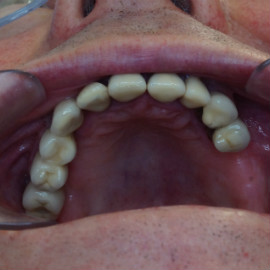

Brakujących pięć zębów dolnych w odcinku wargowym. Rekonstrukcja tkanek i rehabilitacja protetyczna.